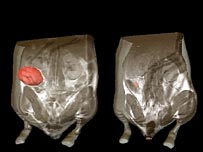

A tumour in a mouse shrank after the gene was reactivated

Two groups of US researchers reactivated the gene in the lab, and found that was enough to make various types of tumour start to shrink.

In animal experiments, they showed that even briefly reactivated, the gene dramatically reduces the size of the tumours, in some cases by 100%.